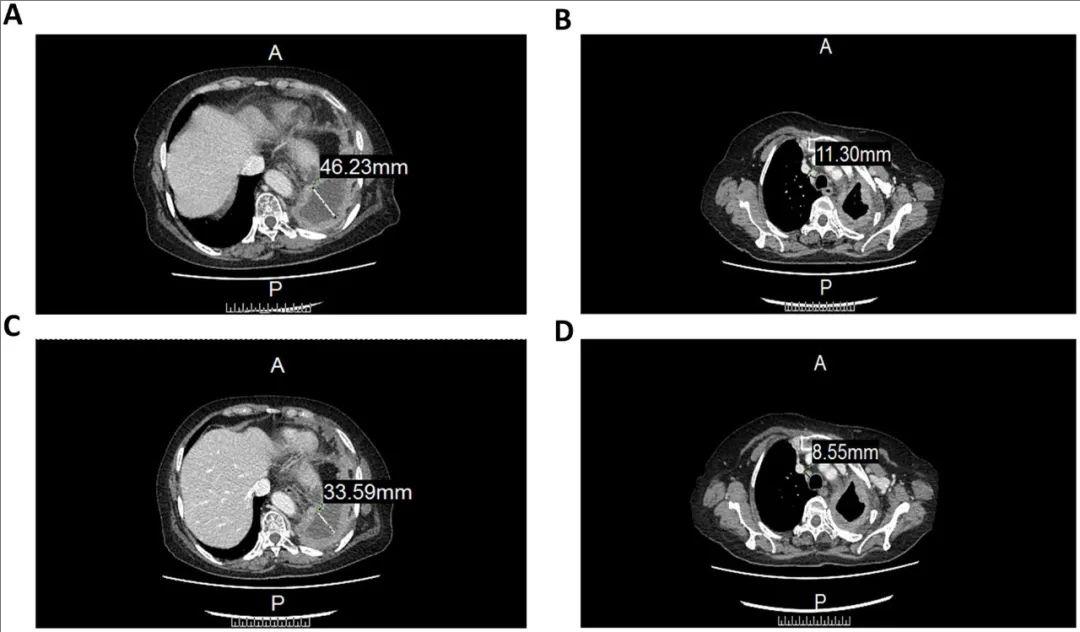

治疗后结果显示,CCCR-NK92细胞对肿瘤有一定的疗效,肿瘤病灶出现缩小表现。CT图像显示,左肺包裹性胸腔内液由46.22mm,减少至33.59mm(图1A、C),前气管-后腔静脉间质面积淋巴结由11.3mm,减少至8.55mm(图1B、D)。

图1 CCCR-NK92细胞治疗前后CT图像对比

▲图源“Sage Journals”,版权归原作者所有,如无意中侵犯了知识产权,请联系我们删除

注:

①图A:CCCR-NK92细胞,治疗前CT图像。

②图B:一轮CCCR-NK92细胞治疗后的CT图像。

③图C:一轮细胞治疗后的CT图像。

④图D:两轮细胞治疗后的CT图像。